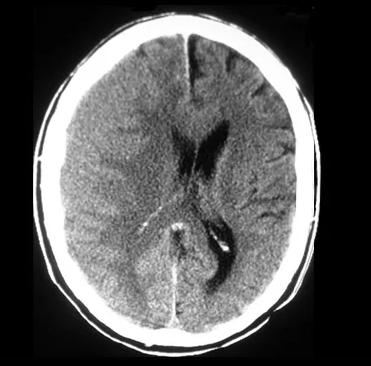

影像总结头颅ct基本知识与常见病变

脑部ct照片真实

脑出血头部ct图片

头颅CT图片